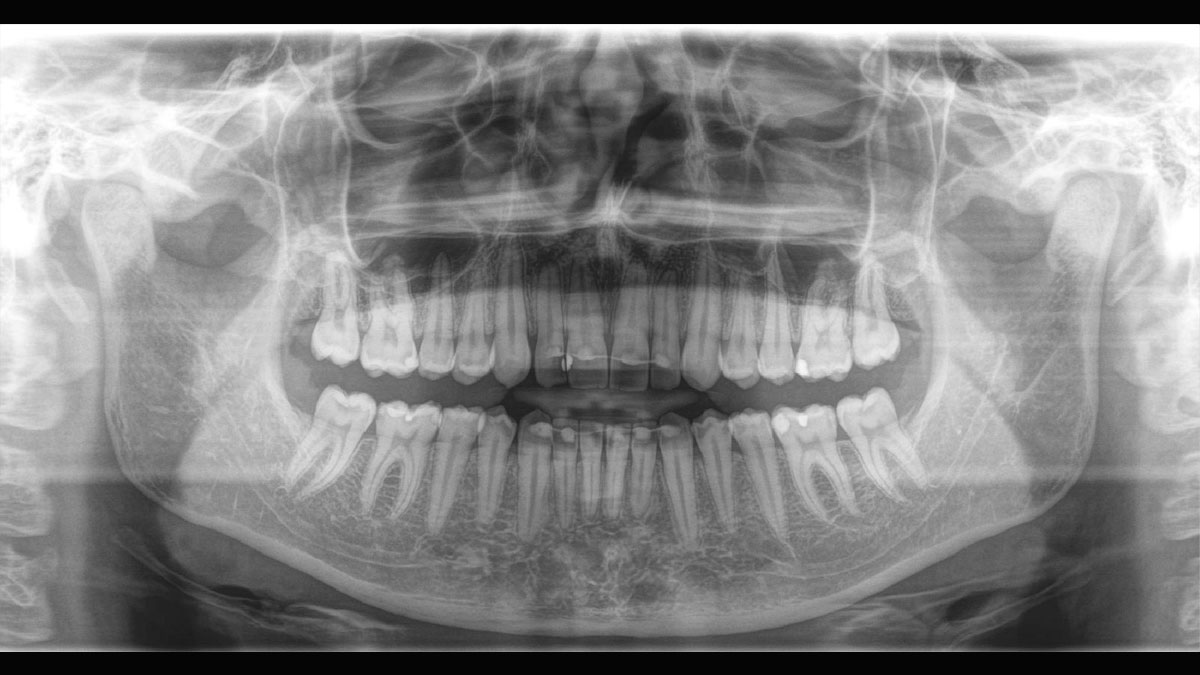

Der 2D/3D Power Performer Orthophos SL ist eine großartige Wahl für alle, die einfach mehr wollen. Der integrierte Direct Conversion Sensor (DCS) wurde für anspruchsvolle Bildqualitätsstandards entwickelt und bietet detaillierte Daten. Der intelligente Autofokus liefert automatisch fokussierte Panoramabilder mit hervorragender Gesamtschärfe. Orthophos SL bietet höchsten Bedienkomfort durch automatische Positionierung, eine anwenderfreundliche, intuitive Bedienung mit dem EasyPad und ein individuell einstellbares Umgebungslicht für ein exklusives Erscheinungsbild.

Der Direct Conversion Sensor erfüllt besonders hohe Standards für die 2D-Bildgebung

Der Autofokus erzeugt aus mehreren tausend Einzelbildern automatisch eine beeindruckende scharfe Panorama-Röntgenaufnahme

Der Direct Conversion Sensor (DCS) hat den Standard der Panorama-Bildgebung neu definiert. Röntgenstrahlen werden direkt in elektrische Signale umgewandelt – im Gegensatz zu herkömmlichen Systemen gibt es keinen Signalverlust durch Lichtumwandlung, was eine verbesserte Bildgebung ermöglicht. Das Ergebnis sind Bilder mit einer sehr hohen Schärfe, selbst bei niedriger Dosis.

Eine Röntgenaufnahme muss sofort diagnostizierbar sein. Der Autofokus hilft dabei erheblich. Orthophos SL erfasst mehrere tausend Einzelbilder in einem Zyklus und erkennt automatisch scharfe Bereiche, um ein gleichmäßig scharfes Gesamtbild zu erzeugen. Der intelligente Autofokus erfordert keine manuellen Arbeitsschritte vor und nach der Erfassung.